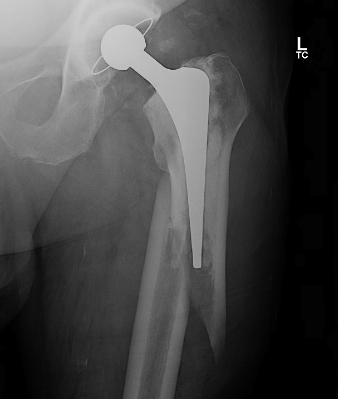

Initial press fit

- implant geometry fits the cortical bone in the proximal femur

- good initial mechanical stability

Biological fixation for success

- good press fit

- minimal micromotion

- bony or fibrous tissue ingrowth or ongrowth